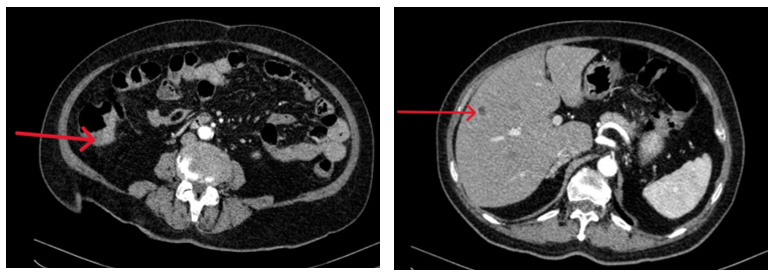

- Chụp CT ổ bụng có tiêm thuốc: Đại tràng lên thành dày 20mm, ngấm thuốc sau tiêm. Kích thước bình thường, bờ đều. Nhu mô gan phải có vài nốt giảm tỷ trọng 5mm ngấm thuốc kém sau tiêm

Hình 3: Chụp CT ổ bụng có hình ảnh dày thành đại tràng lên (bên trái) và nốt ngấm thuốc kém ở nhu mô gan (bên phải)